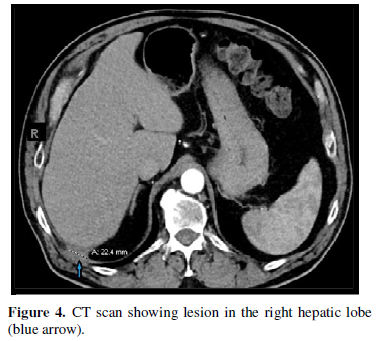

Repeated CT scan of the abdomen and pelvis with and without contrast in November 2019 showed small persistence of soft tissue density focus posterior to the right hepatic lobe with slight increase in the size to 2.2 cm (Figure 4).